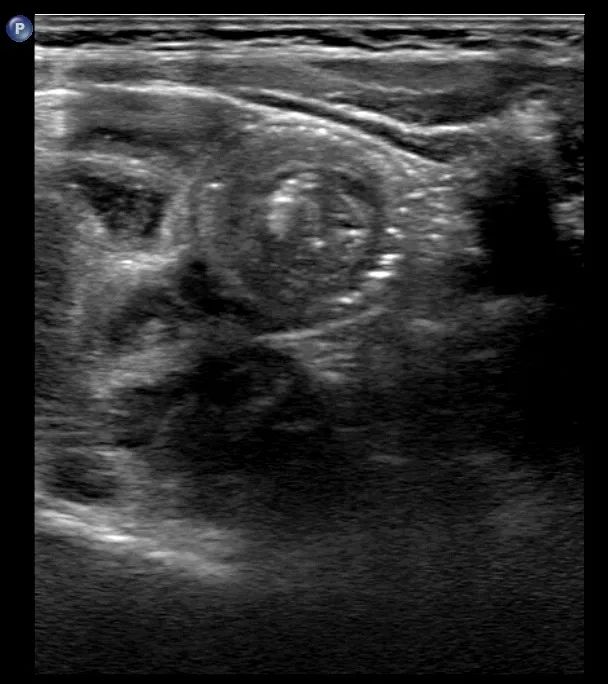

结果显示为典型肠套叠

肠套叠,顾名思义是指一段肠管套入与其相连的肠腔内,并导致肠内容物通过障碍,当肠道蠕动时就会使肠系膜被拉扯,从而引起剧烈疼痛。除引起套入的肠管供血障碍外,还会出现肠蠕动异常,并导致肠梗阻。是婴幼儿时期常见的急腹症之一。